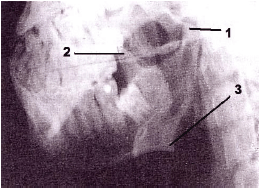

Observe atentamente a figura abaixo e, em seguida, responda à questão.

Trata-se de imagem radiográfica correspondente à incidência de